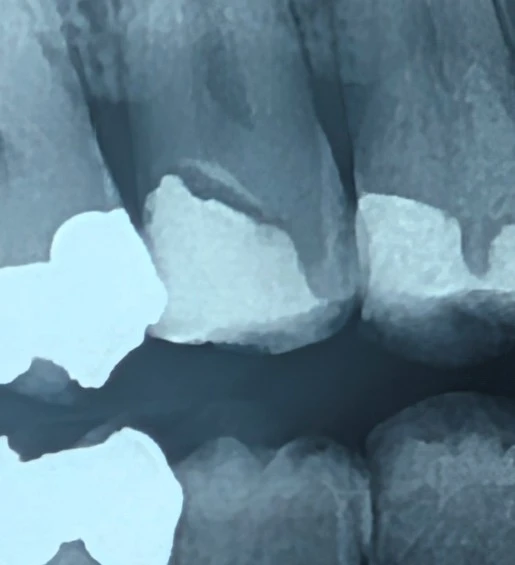

🟦 Insight 23 — وقتی رادیولوسنسی زیر ترمیم، پوسیدگی نیست

رادیولوسنسی منظم زیر ترمیم و تمایز آن از پوسیدگی ثانویه

در رادیوگرافی‌های بایت‌وینگ، مشاهدهٔ رادیولوسنسی در مجاورت ترمیم‌ها می‌تواند بلافاصله ذهن را به سمت پوسیدگی ثانویه هدایت کند.

با این حال، در برخی موارد ناحیه‌ای رادیولوسنت با مرزهای مشخص در زیر ترمیم دیده می‌شود که منشأ آن پوسیدگی نیست، بلکه به مواد ترمیمی مربوط است.

وقتی رادیولوسنسی:

دارای مرزهای صاف و منظم است

ضخامتی یکنواخت دارد

موازی با کف حفره دیده می‌شود

و به‌صورت محدود در زیر ترمیم باقی می‌ماند

احتمال پوسیدگی ثانویه کاهش یافته و تفسیر به سمت وجود لاینر یا کامپوزیت‌های رادیولوسنت هدایت می‌شود.

در پوسیدگی دنتینی انتظار داریم:

حاشیه‌های نامنظم و diffuse

گسترش تدریجی به طرفین

کاهش تدریجی دانسیته

و الگوی انتشار بیولوژیک در امتداد دنتین

در حالی‌که الگوی یکنواخت و مهندسی‌شده، رفتار بیولوژیک پوسیدگی را تقلید نمی‌کند.